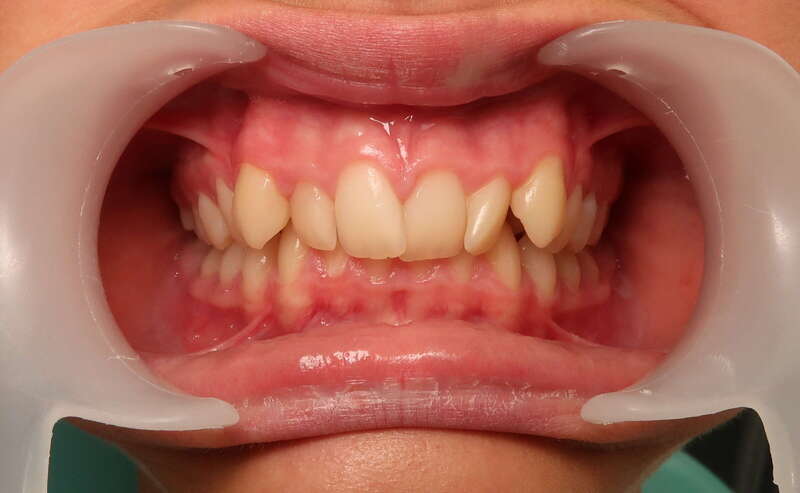

Cas n°1 traité par aligneurs (interception) - enfant

Ce cas d’interception chez un enfant de 8 ans démontre l'efficacité des aligneurs pour corriger des troubles fonctionnels précoces. Le diagnostic présentait des inversions d'articulé provoquant une déviation de la mandibule vers la gauche et un décalage des milieux.

Grâce à une coopération exemplaire et un traitement totalement indolore, l'expansion de l'arcade a permis de recentrer la mâchoire. Cette intervention a littéralement remis la croissance sur les rails, neutralisant le risque d'asymétrie faciale squelettique.

• Correction fonctionnelle : Recentrage immédiat de la mandibule et des milieux inter-incisifs.

• Prévention : Création d'un environnement favorable pour les dents définitives à venir.

• Bien-être : Approche douce respectant le confort de l'enfant.

C'est une étape fondamentale qui simplifie l'avenir orthodontique du patient tout en garantissant un développement facial harmonieux.

Avant

Après